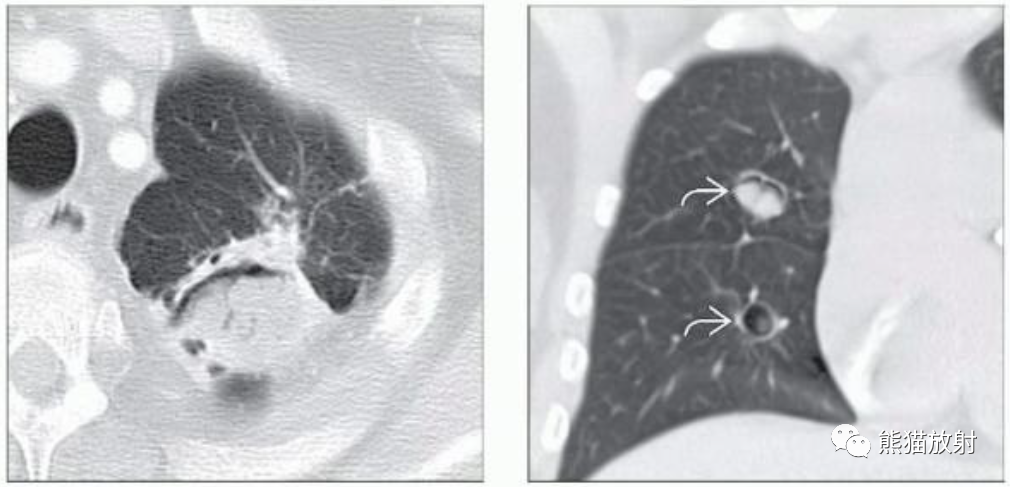

(左) 艾滋病并发肺隐球菌病。CT显示右肺实性和空洞性肺结节。肺隐球菌病最常见的表现是多发性肺结节。空洞在较大的结节和免疫功能低下的患者中更为常见。

(右) 同一患者,气管隆突下淋巴结肿大,表现为环形强化和中心低密度。

(左)免疫功能低下的肺隐球菌病患者,PA胸片显示右下肺野见一空洞性肿块,内见气液平面。

(右)同一患者,CECT肺窗和软组织窗图像显示右肺下叶空洞性肿块,内见气液平面,提示脓肿形成。邻近肺实质可见片状磨玻璃影(弯箭)。